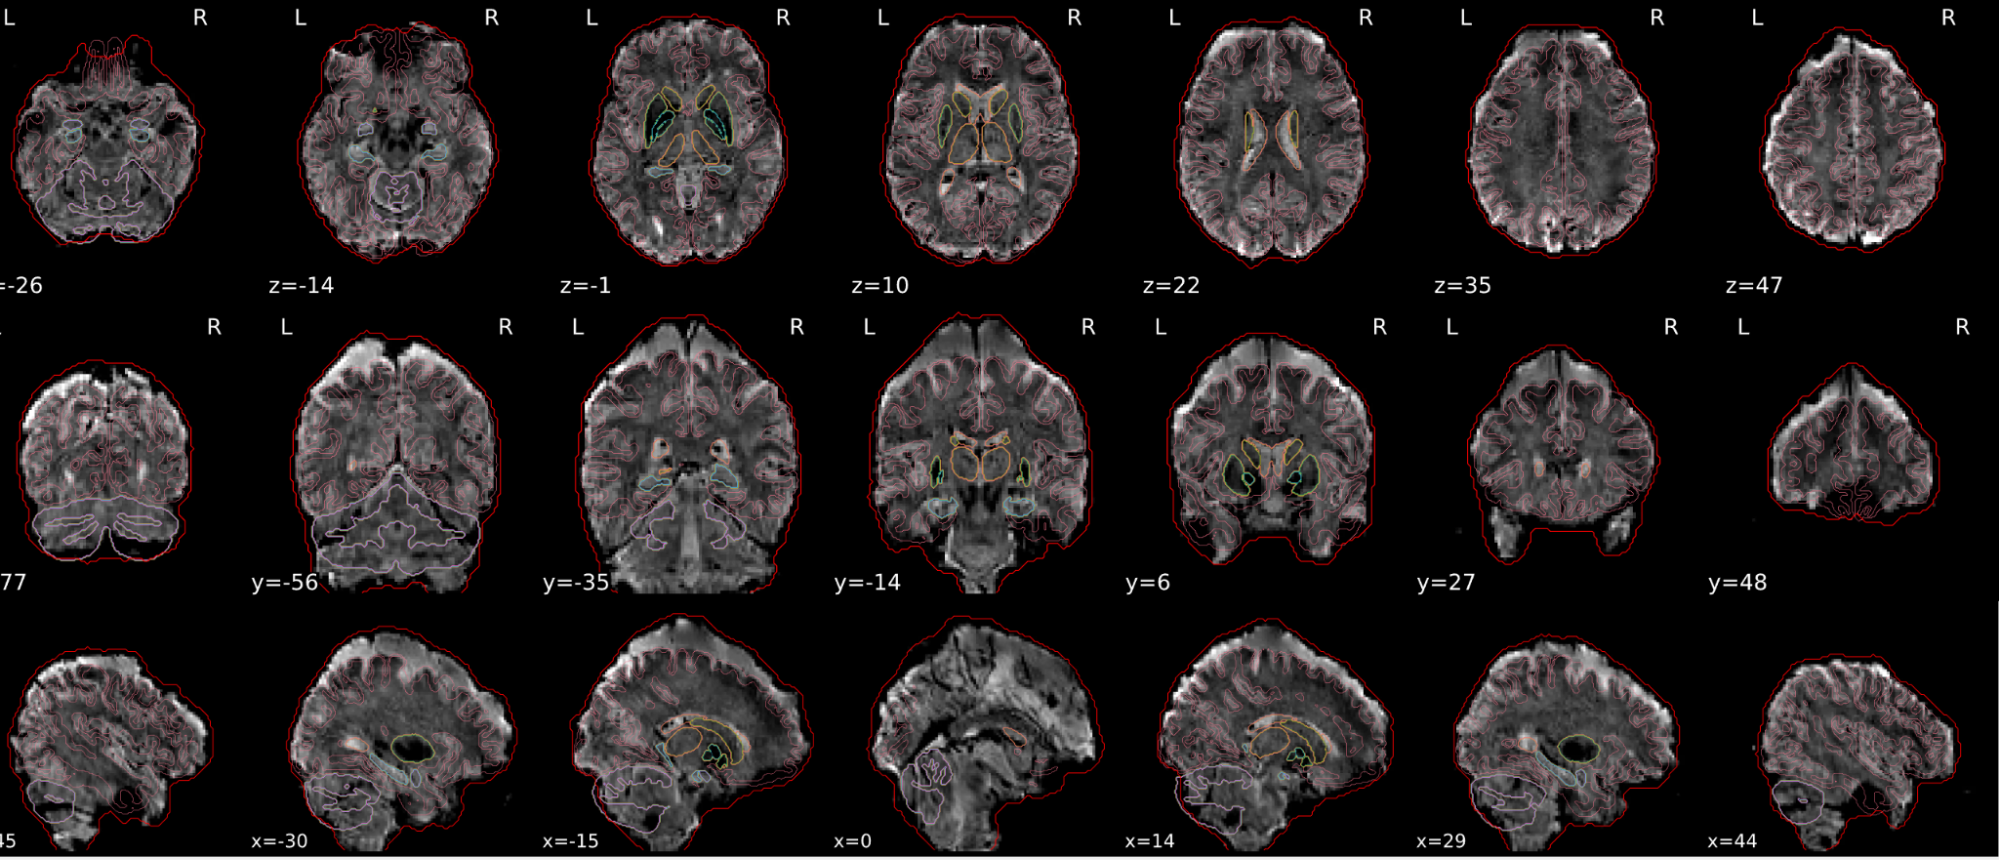

dT1w spatial normalisation

This QC step shows the registration of the T1 image to MNI space.

The registered T1 image is shown in the background with a brain atlas in MNI space as an overlay.

Example of a good subject

- If the registration performed well, you should see an overlap (i.e., correspondence of structures) between the MNI template and the T1 registered to the MNI space.

Example of a bad subject

- In case of poor registration, you should see a misalignment between the MNI template and the T1 (e.g., brain shifted down).

Summary

| good | bad |

|---|---|

| Structures of the MNI template and the registered T1 are well aligned | Structures of the MNI template and the registered T1 aren’t well aligned, e.g. brain is shifted downwards |